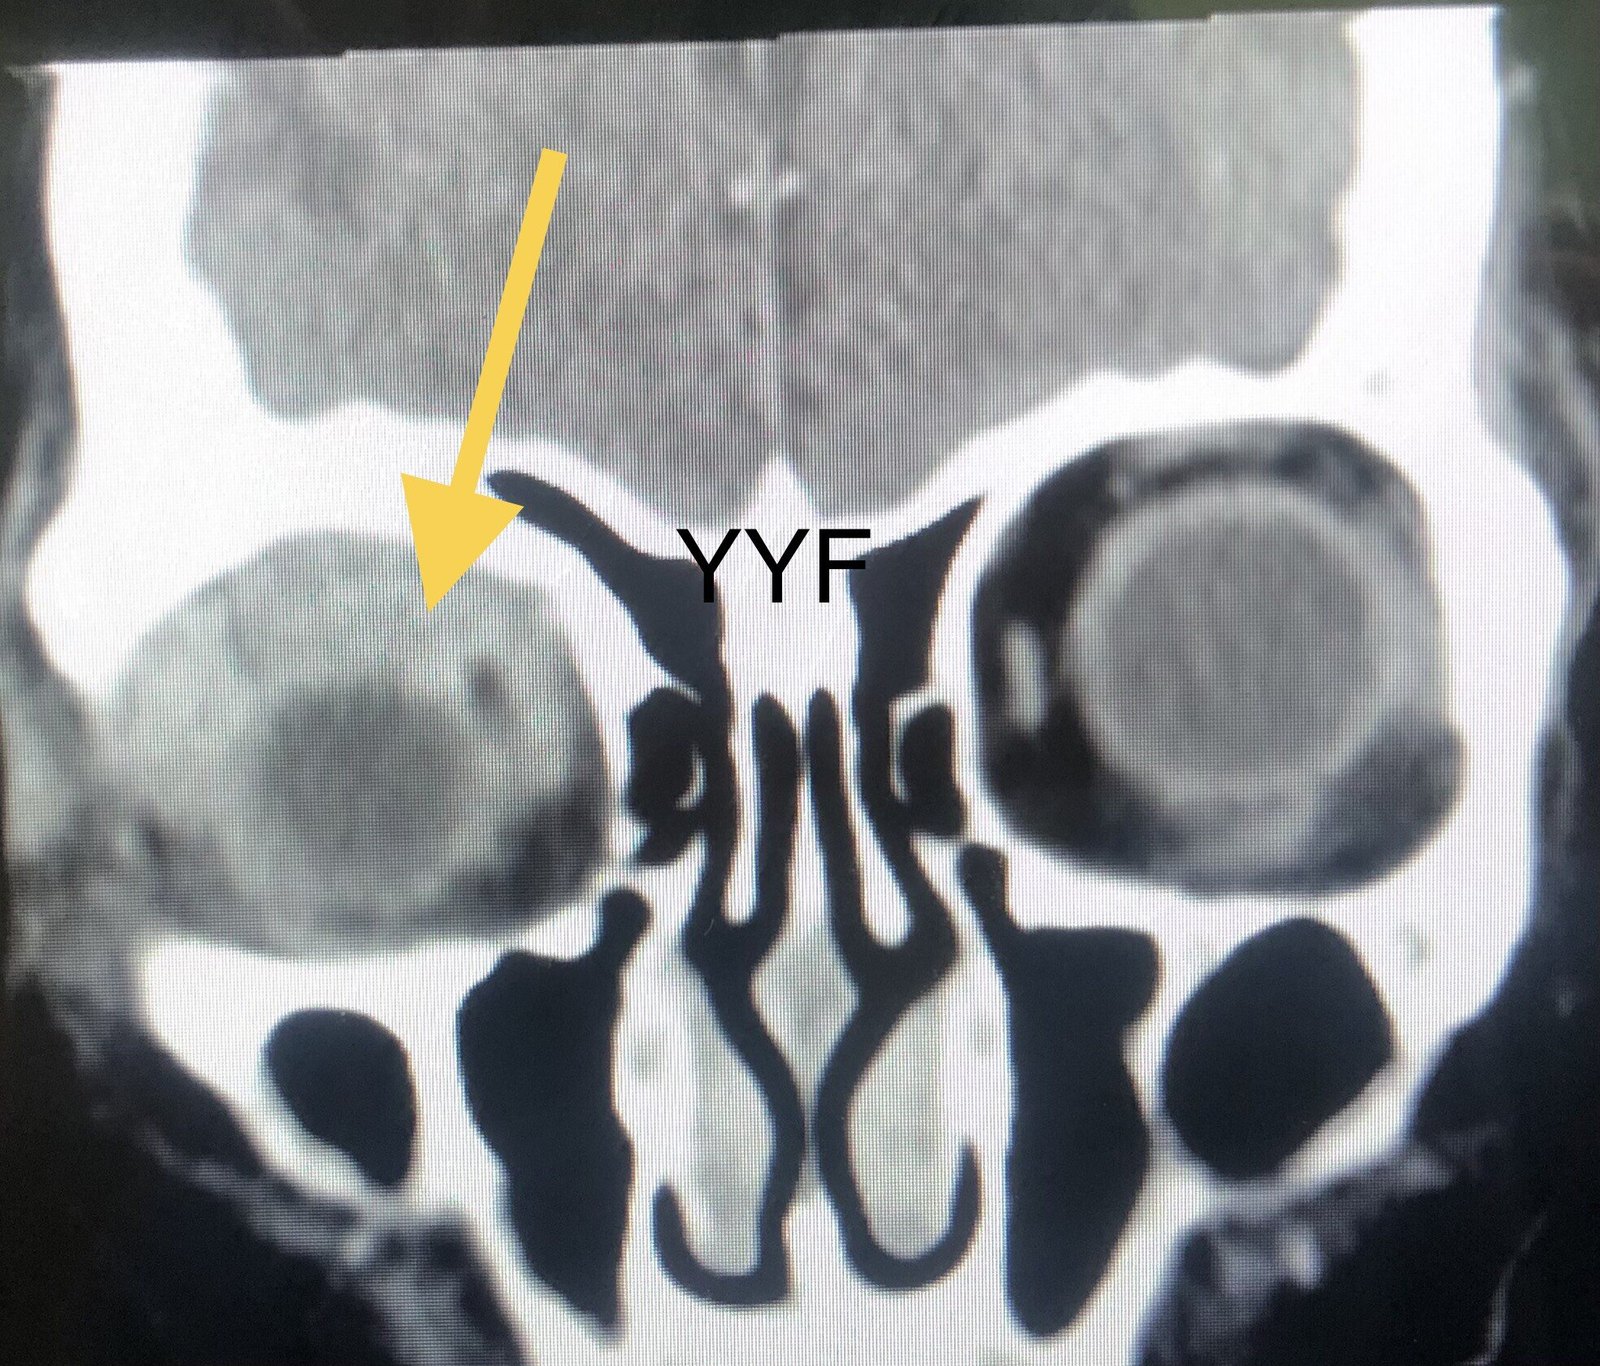

眼眶弥漫性占位

眼眶前段,有包绕眼球生长改变

本例病病变同样累及泪腺区,但远远超出泪腺范围,

病变累及泪腺区,但远超过